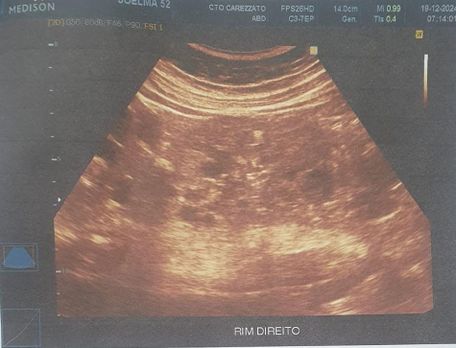

Foi realizado exame de imagem (21/10/2024), ultrassonografia abdominal com os seguintes achados (figura 1.1, 1.2, 2 e 3) Exames laboratoriais (21/10/2024): Acido úrico 2 mg/dl, Bilirrubina total 0,37 mg/dl, Bilirrubina direta 0,18 mg/dl, Bilirrubina indireta 0,19 mg/dl, TGP 21 u/l, TGO 16 U/L, Uréia 34 mg/dl, Creatinina 0,51 mg/dl, Sorologia para hepatite B, C não reagente.

Figura 2 e 3. Rim esquerdo ,apresenta tamanho aumentado , parenquima heterogêneo e contornos irregulares, com dimensoes 13.1 cm x 5.3 cm. Multiplos cistos em ambos os rins, o maior no polo inferior do esquerdo medindo 4.6 cm x 4.4 cm. Rim direito , apresenta tamanho aumentado, parenquima heterogêneo e contornos irregulares, dimensoes 12.0 cm x 5.1 cm.